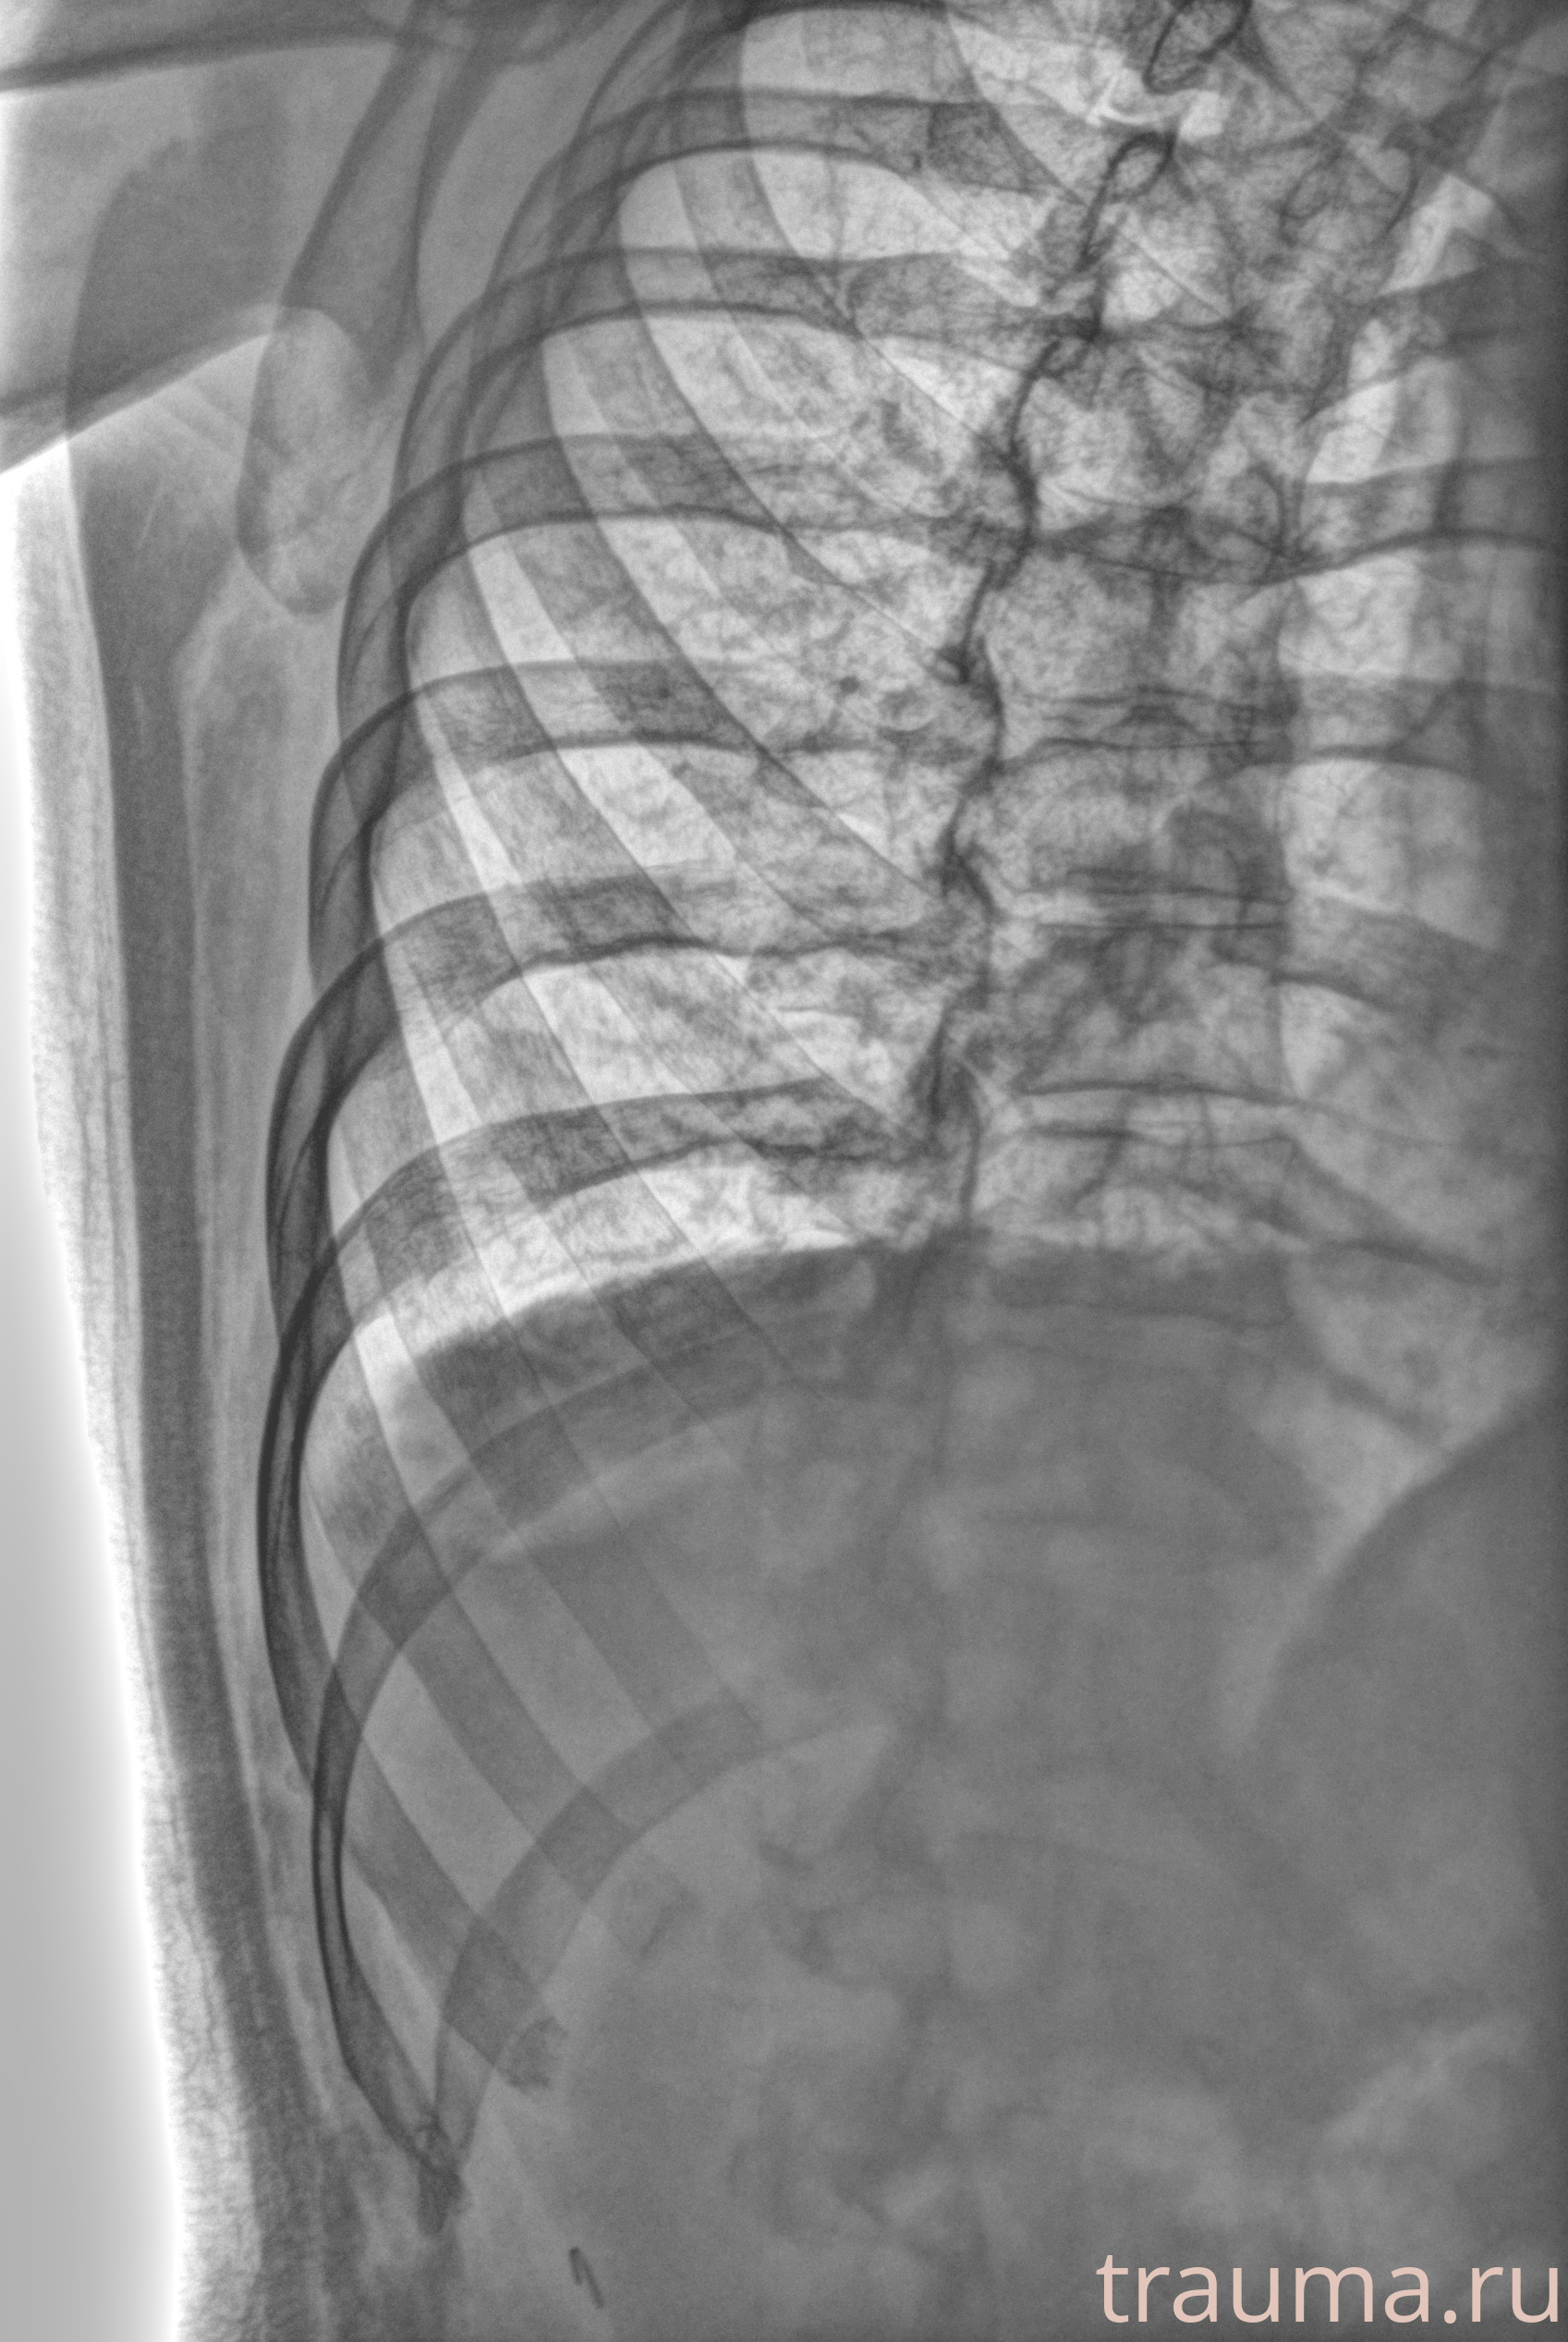

Рентген на дому: по вашему адресу приезжает врач-рентгенолог, травматолог-ортопед с мобильным рентгеновским аппаратом, проводит диагностику травмы или заболевания, делает необходимые рентгенограммы, дает рекомендации по дальнейшему лечению. Получить качественные снимки в домашних условиях возможно благодаря уникальной методике, разработанной МосРентген Центром для института  Склифосовского